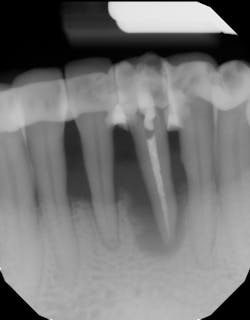

- Splint tooth and adjust occlusion11 (figure 2)

- Proper surgical technique including incision, flap design, and complete detoxification of bony defect and root apices (figures 3 and 3a)